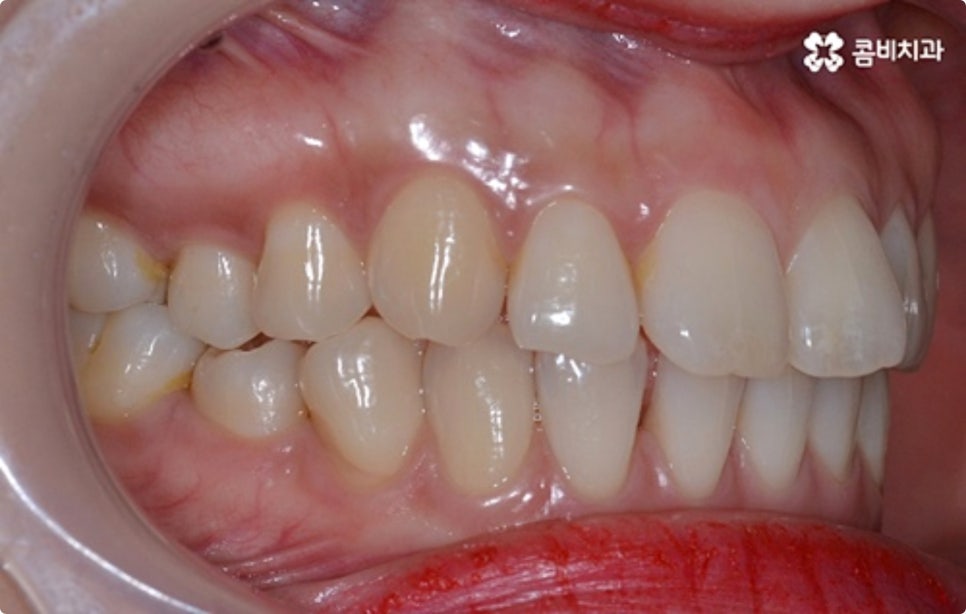

출처 아카이브 열기타인과 대화를 하거나 웃을 때 자연스럽게 보이는 치아는 첫인상에 큰 영향을 주기 때문에 심미적으로 굉장히 중요하다고 볼 수 있습니다. 희고 고른 치열을 가지고 있다면 단정하고 호감가는 인상을 주는 반면 비뚤어진 치열을 가지고 있으면 자신도 모르게 위축이 되어 웃을 때 손으로 입을 가리게 되는 등 콤플렉스가 생길 수도 있는데요.

그렇기 때문에 특히 업무상 대인 관계가 활발한 분들의 경우 직장인치아교정 을 고려하시는 분들이 많이 있어요. 심미적인 이유 때문 만이 아니라 돌출입, 주걱턱 등 부정교합 증상으로 불편함을 겪고 있다면 기능적으로도 문제가 될 수 있으며 이는 시간이 지날수록 악화될 가능성이 있으니 될 수 있는대로 빨리 직장인치아교정 을 통해 바로 잡는 것이 구강 건강을 위해서도 좋을 거예요.

클리피씨 교정도 치아 색상의 세라믹 재질을 사용하기 때문에 심미성이 높은 편이지만 만약에 장치가 아예 겉으로 드러나지 않았으면 좋겠다고 생각하신다면 브라켓을 치아 안쪽에 부착하는 설측교정을 이용할 수 있는데요. 하지만 설측교정은 혀와 맞닿는 부분의 이물감, 통증, 발음상 문제 등을 일으킬 수 있기 때문에 잘 보이는 윗니는 설측으로, 잘 드러나지 않는 아랫니는 보통 교정과 같이 순측 (입술쪽) 으로 진행하는 콤비교정을 통해 이를 보완할 수 있어요. 사진에서 살펴보실 수 있는 케이스 역시 이렇게 콤비로 진행한 직장인치아교정 과정으로 시간이 지날수록 점차 치열이 가지런해지고 교합이 올바르게 개선되는 것을 확인해 보실 수 있습니다.